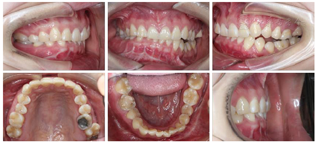

口内检查(图2):

恒牙列,磨牙关系左侧近中,右侧中性,前牙Ⅲ度深覆合,覆盖正常,下颌中线右偏1 mm,左侧前磨牙区开

。

正面观:下颌不对称,颏部右偏6 mm,微笑时露齿不足,咬合平面左低右高。

侧面观:直面型,双侧下颌升支形态不一致。

开口型左偏,开口度正常。